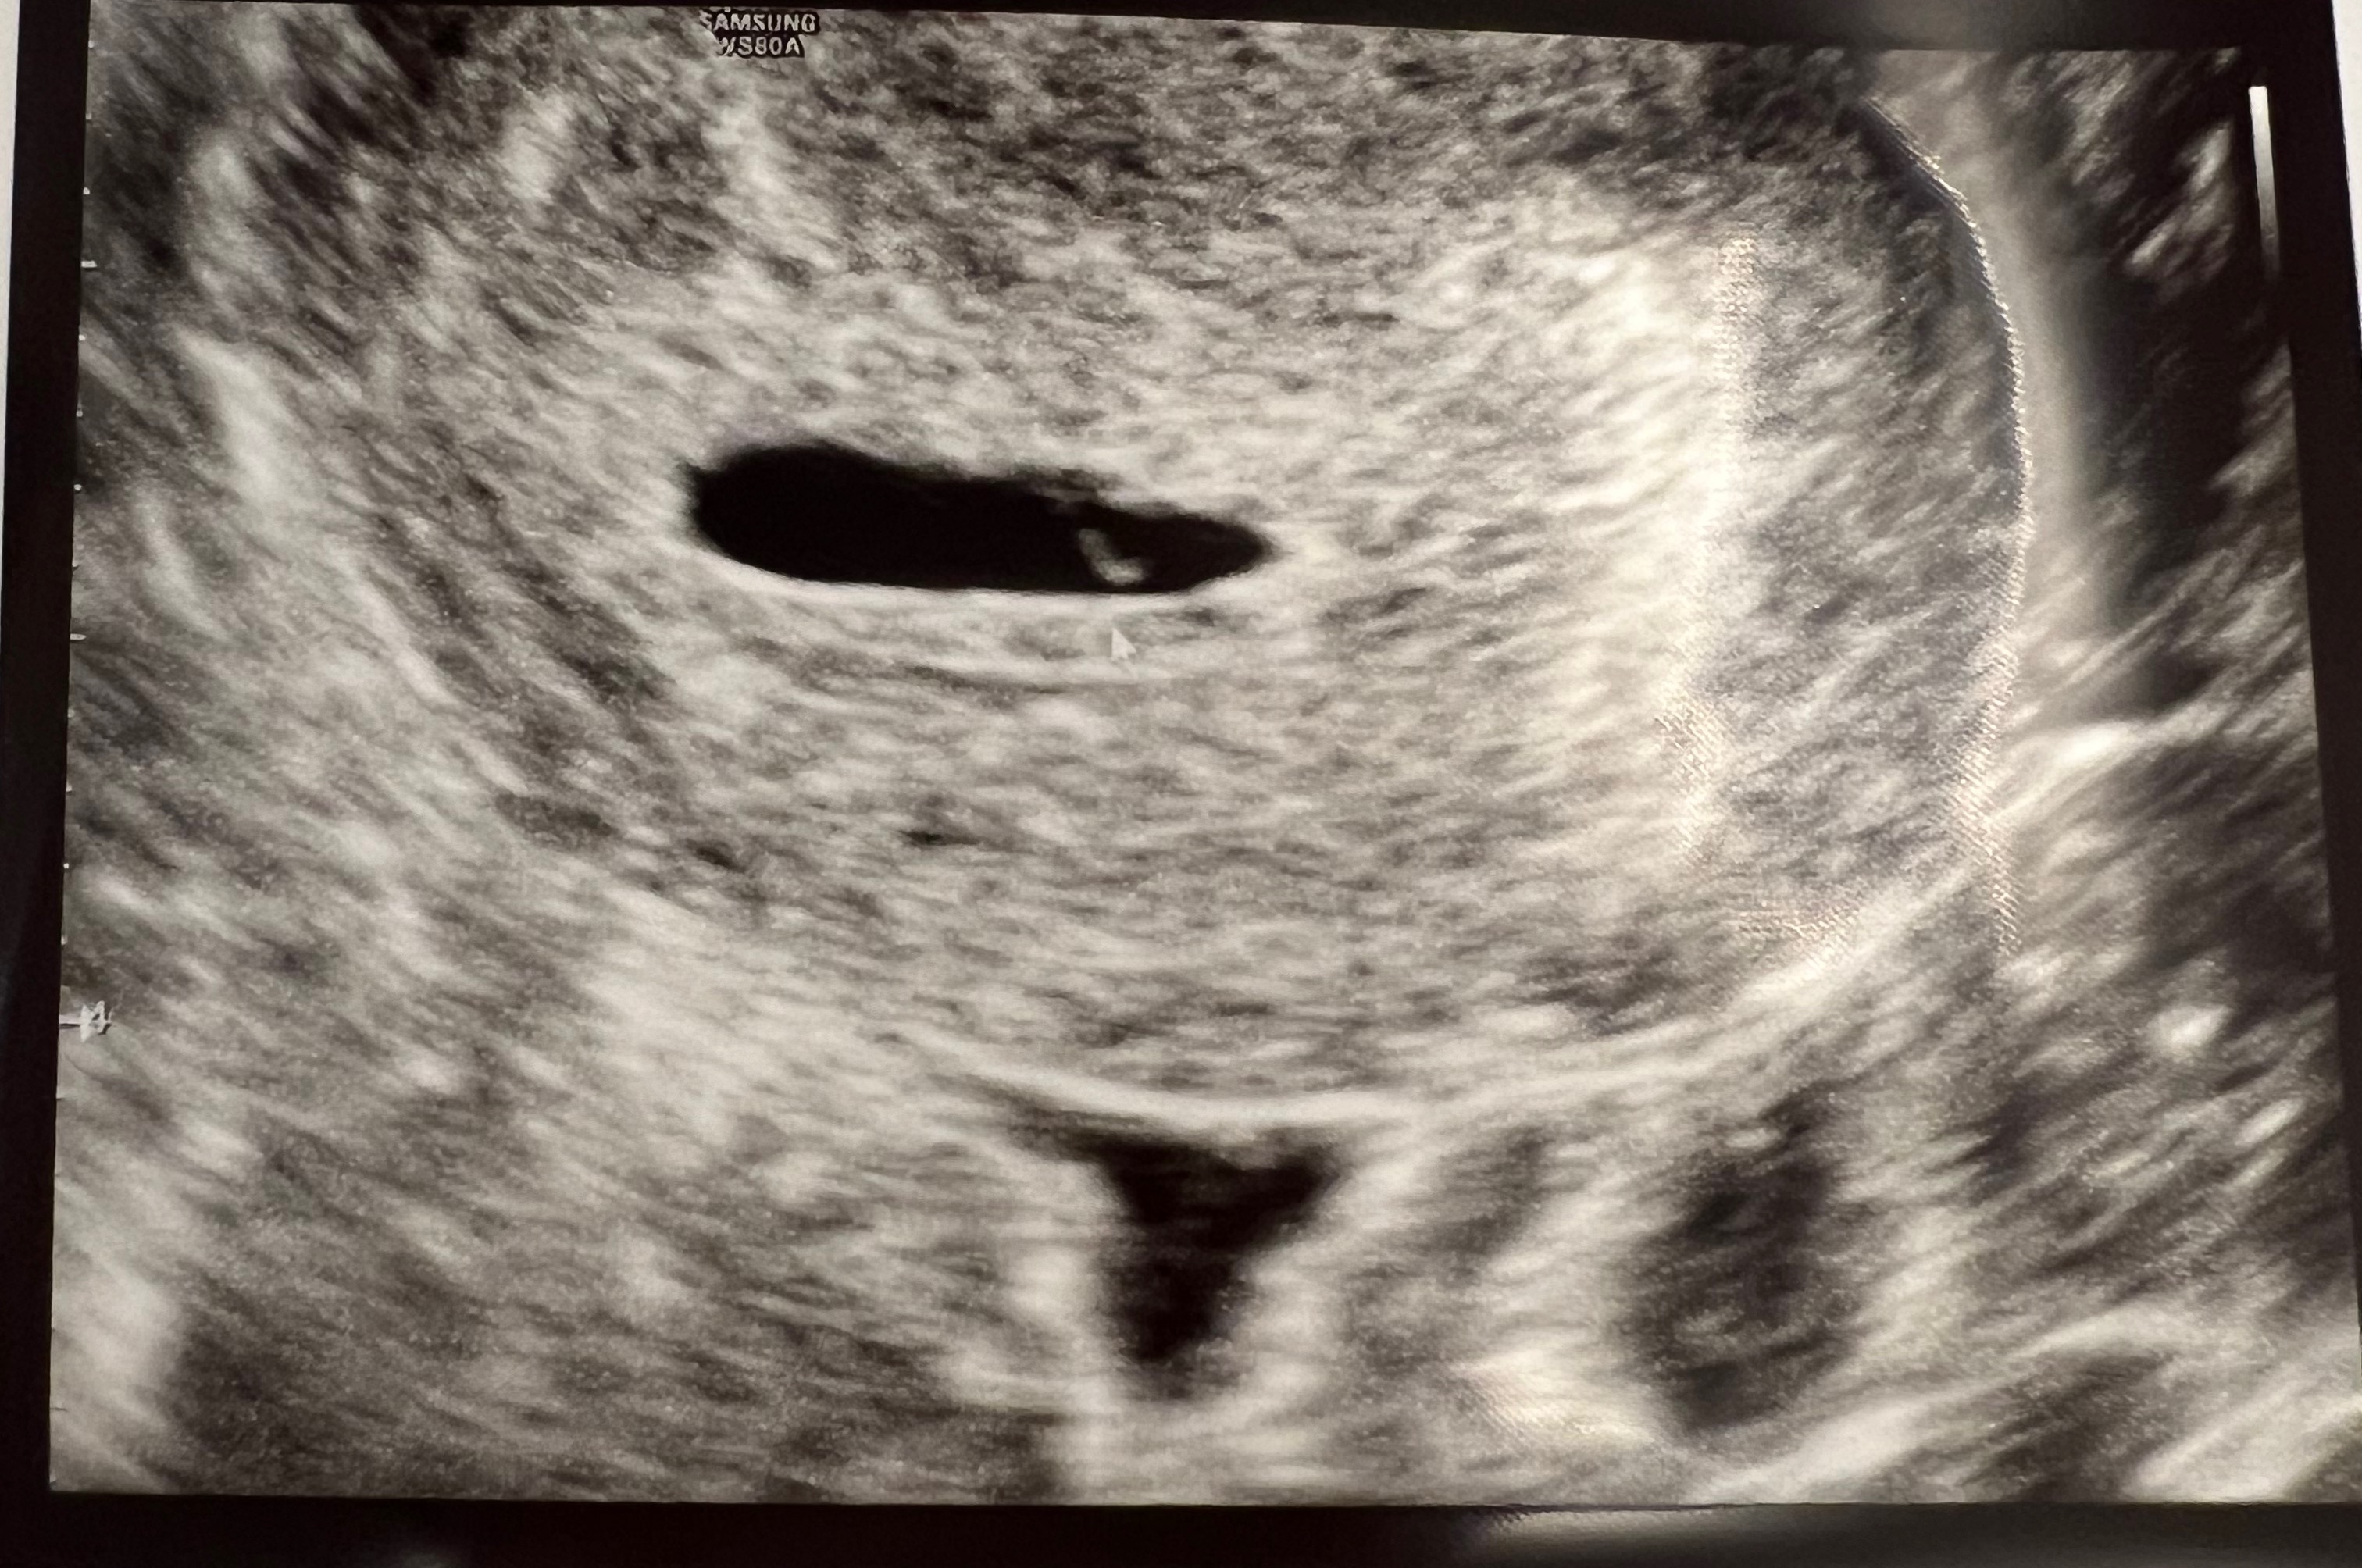

또 퇴근하고 오빠랑 긴장된 마음으로 산부인과에 가서 초음파를 봤는데

이번엔 아기집이 딱^^ 보였다.

옆으로 길게 찍혔지만, 우리 꾸미 아기집이랑 난황을 확인했다.^^

내가 다낭성이 심했던 터라 임신 몇 주 차인지 정확하진 않지만

5주 차인 것 같다고 하셨고, 2주 뒤에 심장소리를 듣자고 하셨다.